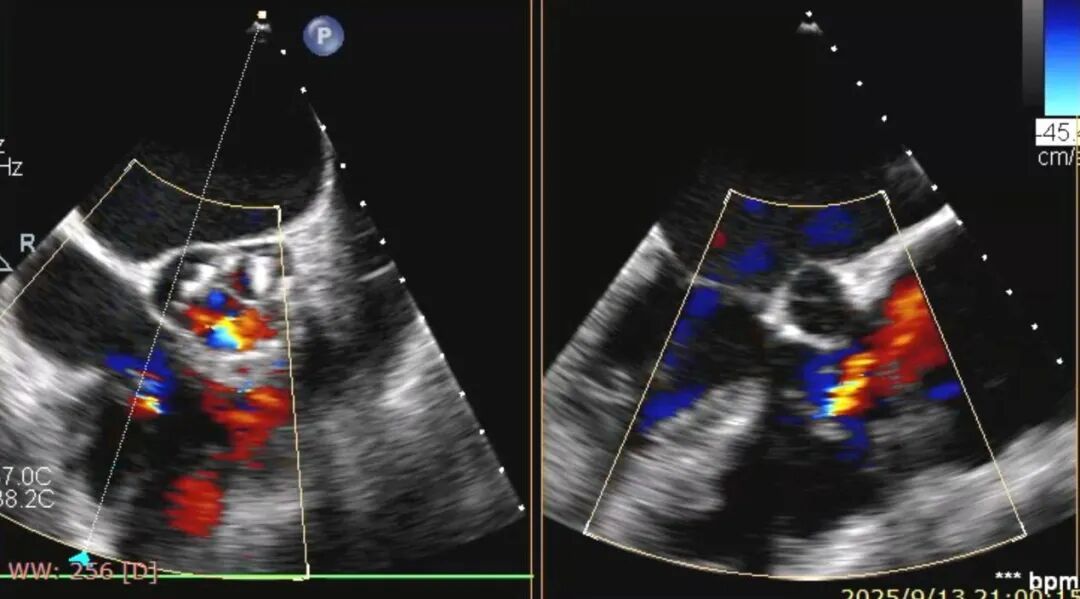

术前食道超声提示三尖瓣重度反流。

术后食道超声提示反流情况明显好转。

手术当天,术前经心脏超声及CTA检查,患者三尖瓣环扩大明显,反流位置复杂。手术团队根据影像结果精准规划,分别于后瓣环及前、后瓣环处植入两枚K-Clip夹合装置,就像在心脏的后背“门框”和前后交界各夹一枚“夹子”,增强瓣叶对合。术中,患者血流动力学稳定,手术顺利完成。术后即时评估显示,患者心脏由原来的“大漏水”变成“轻微渗水”,喘和肿也明显减轻。手术效果显著,患者症状迅速缓解。